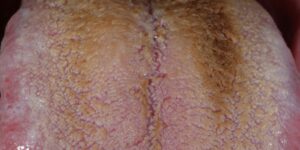

Sintomas de Bócio: O Bócio causam sinais e sintomas. Quando ocorrem sinais e sintomas, eles podem incluir:

- Um inchaço visível na base do pescoço que pode ser particularmente óbvio quando você se barbear ou se maquina

- Uma sensação apertada na garganta

- Tosse

- Rouquidão

- Dificuldade em engolir

- Dificuldade ao respirar